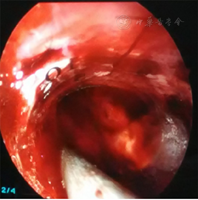

所有患者均在入院后24 h内[4]全麻下行手术治疗。试验组患者术前行头颅CT 1 mm薄扫(图1)、刻盘,并将数据录入神经导航系统;患者全麻取仰卧位,头偏健侧,头架固定并取颅骨标记点进行导航注册,定位手术最佳点,铺单消毒。在患侧颞部切开3~4 cm皮肤切口,充分止血钻孔,切开硬脑膜,通过导航引导组织导管扩张器穿刺至血肿腔内(见封四,图2、图3),取出管芯,将内镜沿组织导管扩张器通道进入血肿腔,由内镜将组织扩张器引导至血肿腔底面,使用吸引器抽吸底面血肿(见封四,图4),直至显露脑组织,向外渐退出组织扩张器,此时见周围血肿回缩至中央,继续抽吸并逐渐退出,依此方式逐渐抽吸血肿至清除完毕,并完全退出扩张器。遇到活动性出血时给予电凝止血,并给予少量明胶海绵覆盖;在创面渗血的地方给予速即沙及少量明胶海绵覆盖。血肿清除完毕后,通过内镜观察残腔无出血及渗血,留置引流管,缝合头皮术毕。